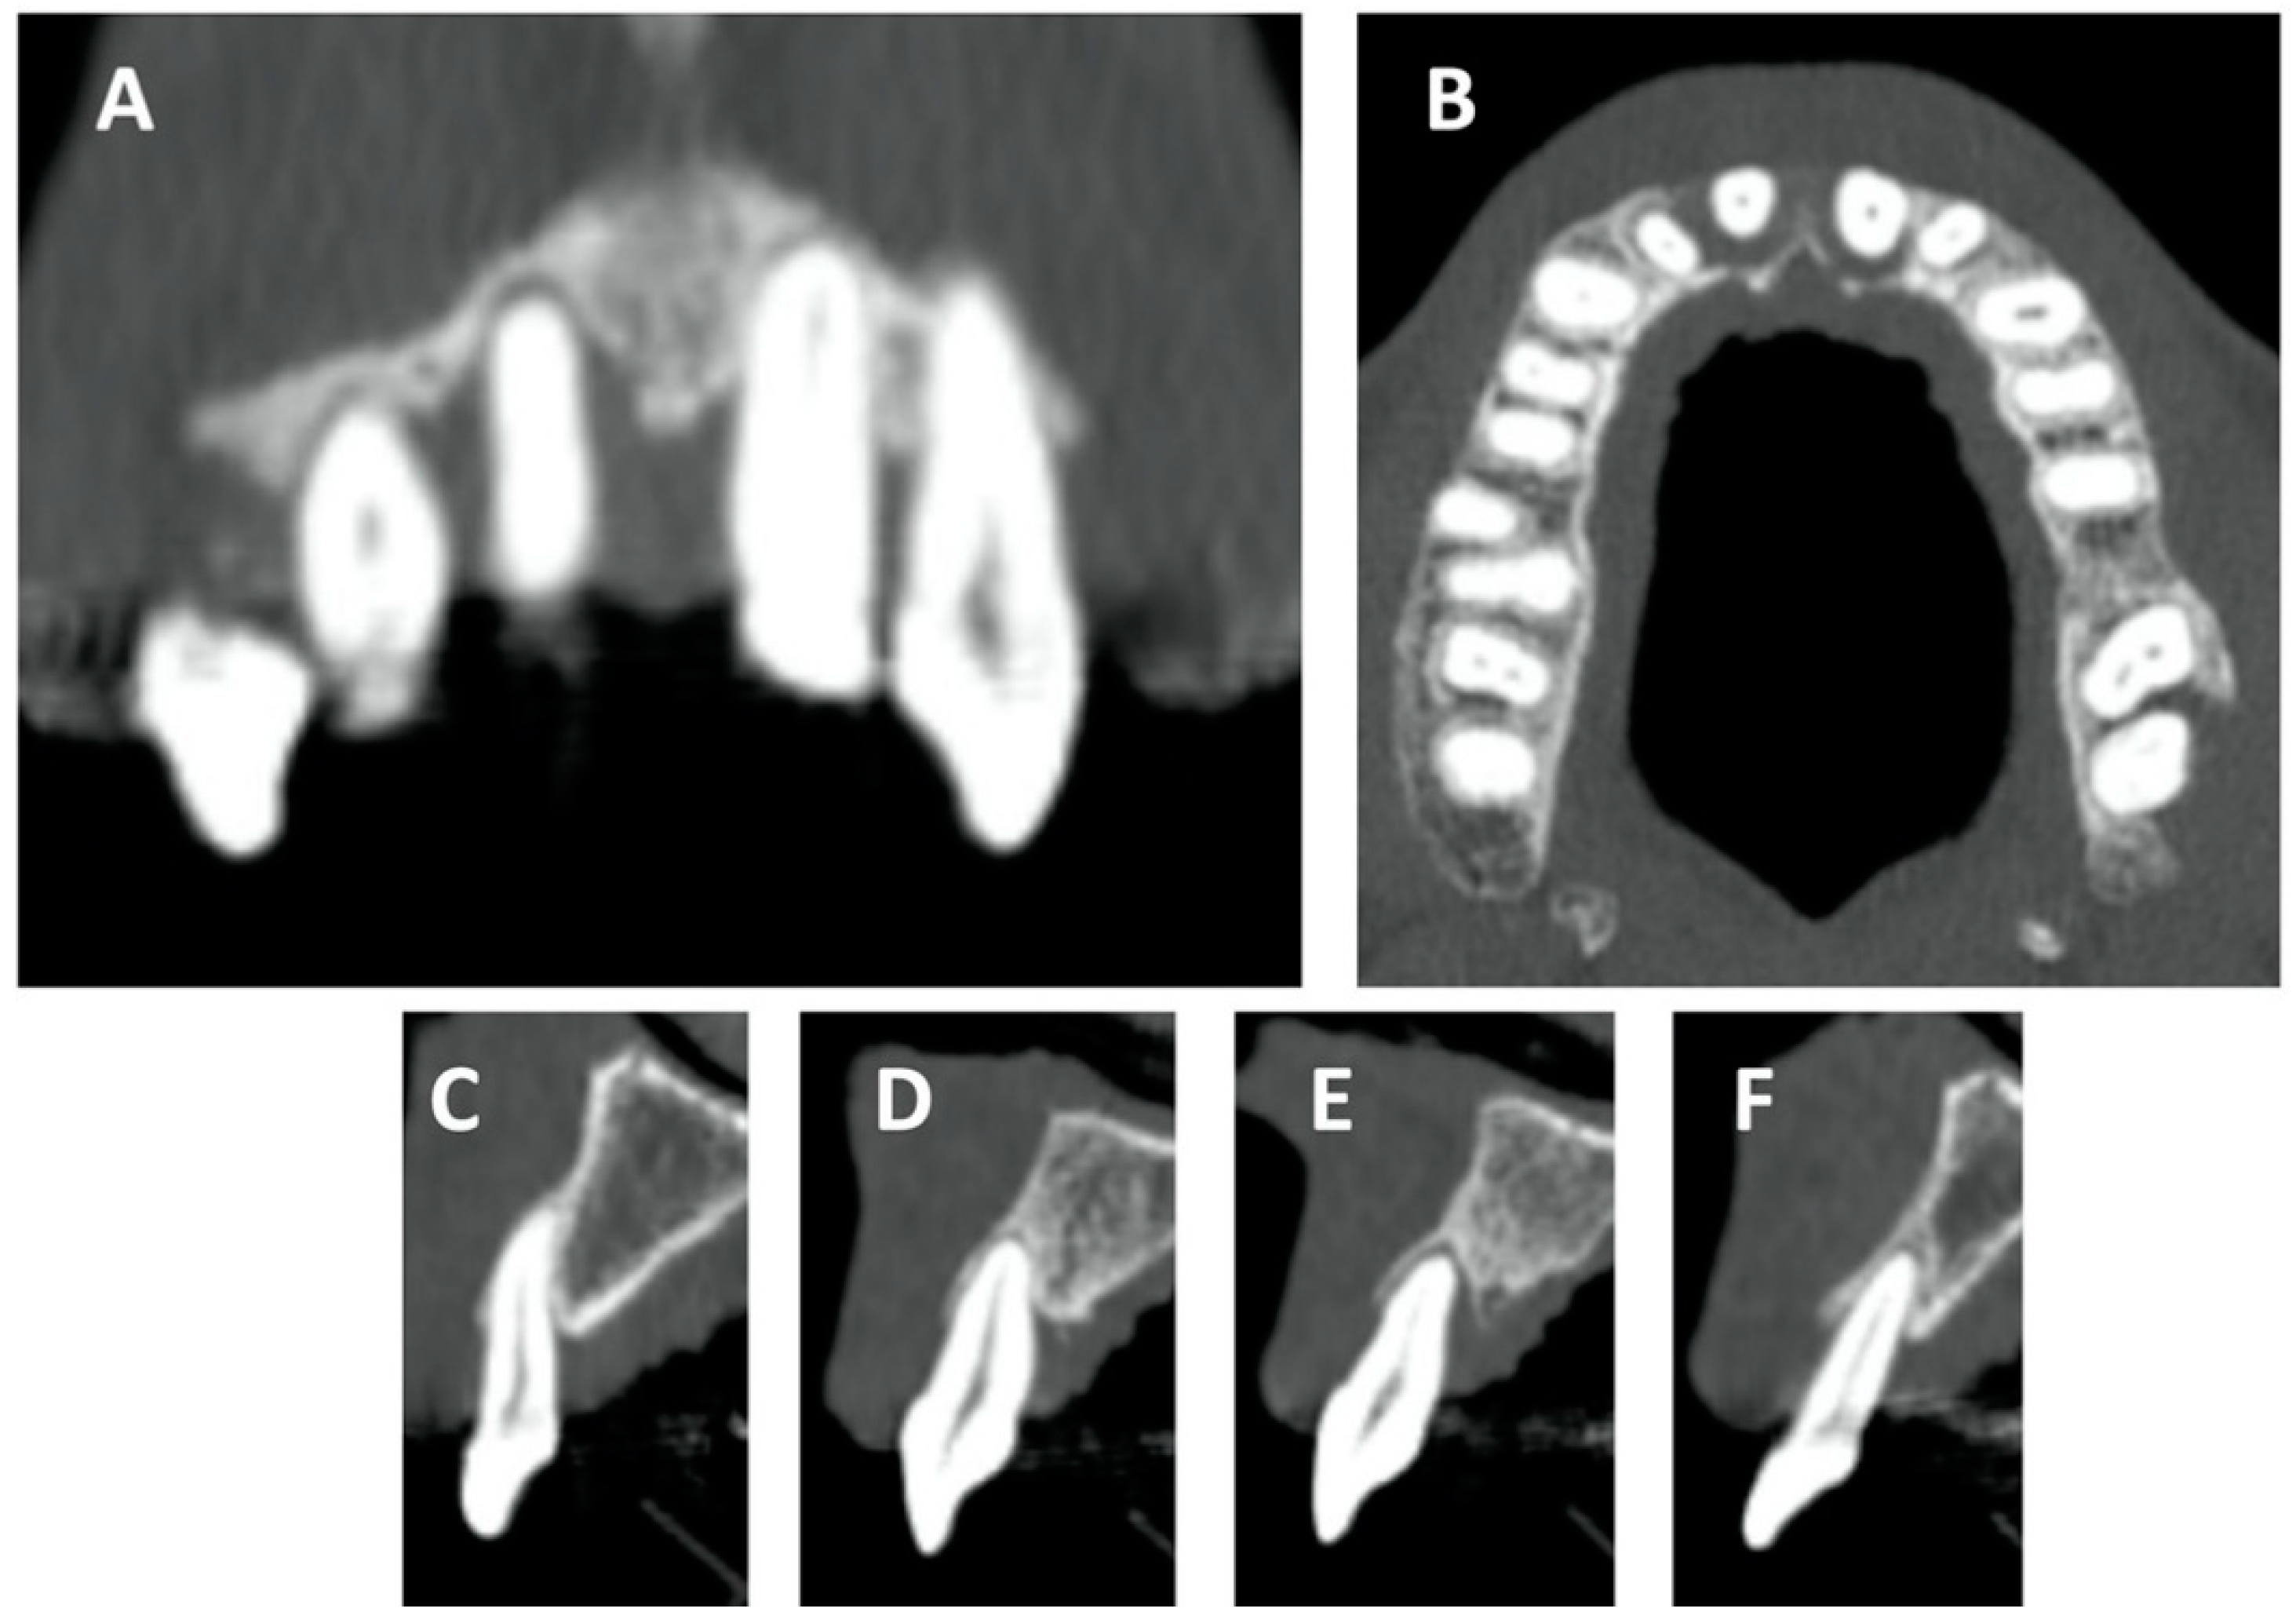

2. Case Report